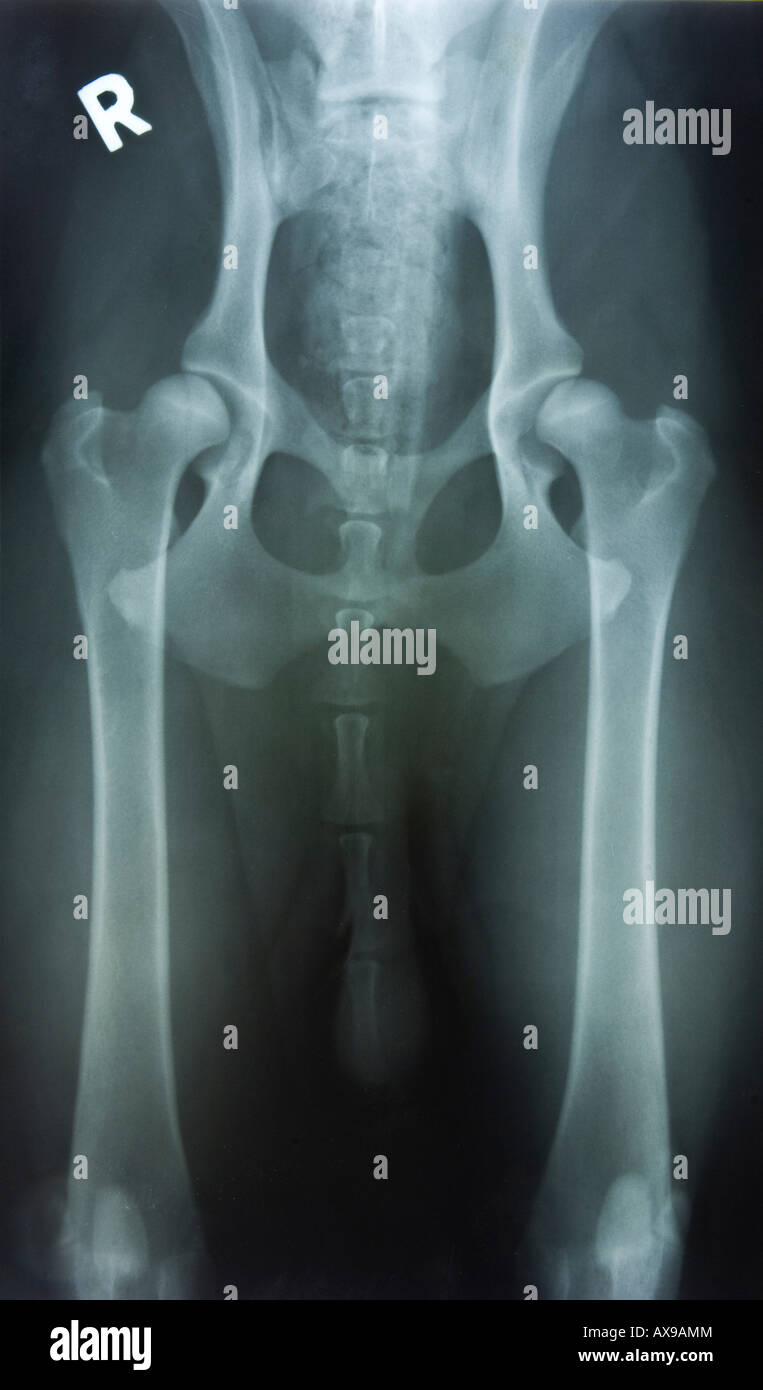

La dysplasie peut se remarquer très tôt chez le chien, lorsqu'il est encore chiot Examen radiographique: chien tranquillisé ou anesthésié (dès 4 à 5 mois)

Ce n'est pas facile, je le sais ; mais ce qui compte avant tout est de. La hanche est l'articulation reliant les pattes arrières du chien à son bassin : elle est formée par le creux du bassin (cotyle) dans laquelle s'emboîte la tête de l'os fémoral (fémur) du chien. Vous avez adopté un adorable chiot, mais il est de race prédisposée à la dysplasie des hanches… Voici ce que vous devez absolument savoir : En résumé : La dysplasie coxo-fémorale juvénile (DCF) est une laxité exagérée des hanches, le plus souvent asymptomatique, chez des chiots de moins de 5 mois

Troubles du comportement chez un chiot de 4 mois Clinique Vétérinaire du Front de Mer. Les jeunes chiots peuvent montrer des signes de boiterie intermittente, de difficultés à se lever ou à monter les escaliers. La dysplasie peut se remarquer très tôt chez le chien, lorsqu'il est encore chiot